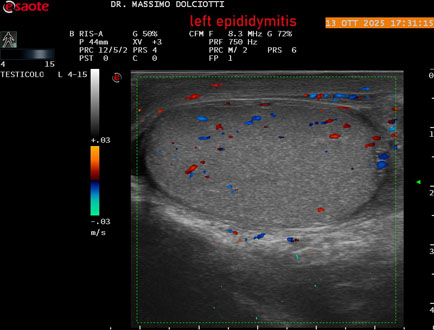

Data inserimento: 14/10/2025

Ecografia del: 13/10/2025

Strumento: Esaote MyLab Eight

Sonda: Lineare Multifrequenza 4-15 MHz

Età Paziente: M 70 anni

Motivazione dell'esame: da 2 giorni dolore al testicolo sinistro.

Commento all'esame: le immagini ed il video documentano l'epididimo sinistro spiccatamente aumentato di volume e di vascolarizzazione, come da flogosi. Didimo sinistro lievemente aumentato di volume. Quadro clinico ed ecografico da ricondurre ad epididimite acuta sinistra.

Conclusioni: epididimite acuta sinistra (acute left epididymitis).

Presentazione: Dr. Massimo Dolciotti - Ancona